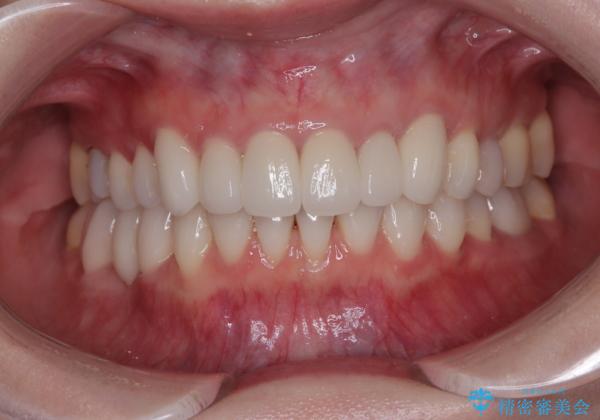

矯正治療自体はインビザラインで満足のいく仕上がりとなりました。

全顎的に満足のいく仕上がりとなりました。